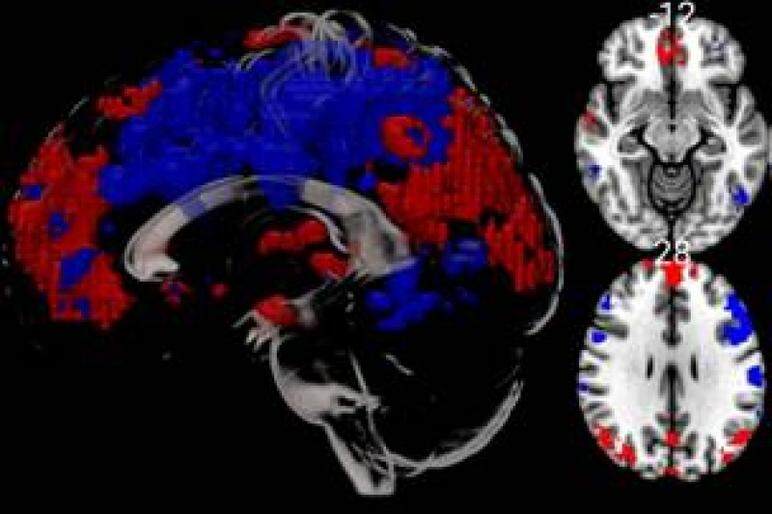

The first research patient has been scanned in BU’s MRI scanner, as part of a study investigating the effects of cold water on brain activity.

The research project is being undertaken by the Department of Psychology at BU, the Faculty of Science and Health at Portsmouth University, University Hospitals Dorset NHS Foundation Trust (UHD) and the Institute of Medical Imaging and Visualisation (IMIV) at Bournemouth University.

It is investigating the effects of cold-water immersion on brain activity, which could provide evidence for whether activities such as cold-water swimming have benefits for managing mental health conditions.

The project is one of several funded through the IMIV MRI pump priming scheme. Associate Professor Dr Jamie Franklin, Head of IMIV and a Consultant Radiologist at UHD, said: “Scanning our first research participant is an important milestone for the IMIV and BU.

“The MRI scanner is a state-of-the-art piece of equipment which will allow us to support a programme of cutting-edge research. We are looking forward to building our imaging research activity over the coming months, and are working collaboratively with colleagues both within and outside BU to realise this ambition.”

The Siemens 3T MRI scanner was co-funded by BU and the Dorset Local Enterprise partnership, and is located in the Bournemouth Gateway Building.